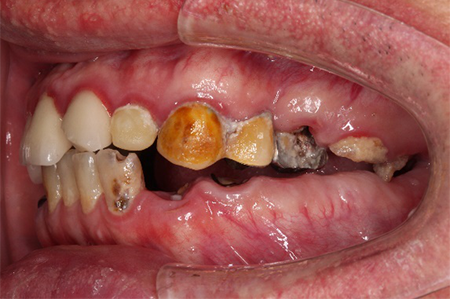

前から見ても歯が欠けてしまい、歯茎も赤く腫れてしまっているのが分かります。

前歯が腫れてしまったと来院された患者様です。

レントゲンを見てみると歯根(歯の根の部分)が黒く溶けていることが分かり、抜歯と診断しました。

前歯のインプラントはとても難しく技術がないと歯茎が下がってしまったりと不具合が出てしまいます。